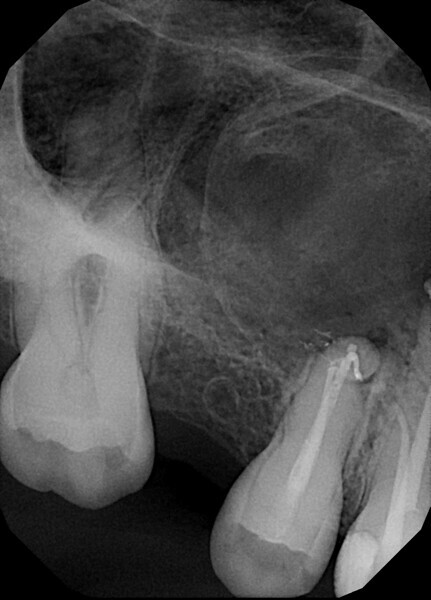

Fig.: 19

Case 2

A 56-year-old patient was referred to our clinic for endodontic treatment of tooth #15. The initial radiograph showed a complex anatomy with abrupt curvatures (Fig. 19). In such cases, our main goal is to avoid breaking the instrument. The in–out technique is a good choice in these situations too. After isolation, the access cavity was created (Fig. 20). Owing to abrupt curvatures in both canals located, a glide path was achieved with manual ISO #8, 10 and 12 K-files (VDW; Fig. 21). During manual instrumentation, small adjustments to the access cavity were made with an ultrasonic tip (Fig. 22).

After manual glide path preparation, final instrumentation with VDW.ROTATE files was performed using the in–out technique (Fig. 23). After preparation and final irrigation, obturation was performed with the continuous wave compaction technique and 2Seal, a root canal sealer on an epoxy–amine resin basis (VDW; Fig. 24). The final radiograph showed the fully obturated root canal complex (Fig. 25).